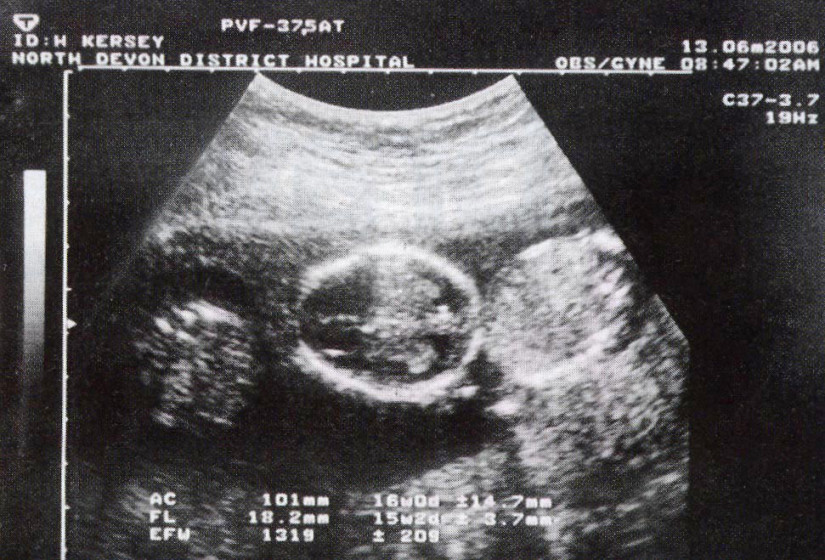

LONDRA – Hannah Kersey è riuscita a dare alla luce tre gemelli da due uteri separati, un vero miracolo secondo i medici, dato che una situazione del genere ha un esito positivo solo una volta su un milione.

La giovane mamma vive con il marito Mick Faulkner a Northam, nel Devon inglese. Hannah Kersey ha due uteri invece di uno: quando i medici le hanno detto che stava in attesa di tre figli, lei e suo marito quasi non ci credevano dato che alla donna avevano sempre detto delle difficoltà ad avere un figlio. I tre gemelli sono tre femmine e sono state concepite da due spermatozoi diversi. E così Ruby e Tully sono identici, mentre Gracie è rimasta sola ed è venuta al mondo con i lineamenti diversi.